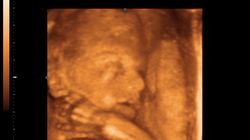

Nisko ułożona główka dziecka w 27. tygodniu ciąży

witam lekarz stwierdził że główka dziecka jest w dól i ze czuje ja nisko pod głowica usg czy to niebezpieczne?czy to normalne.Jest to 27 tydz.